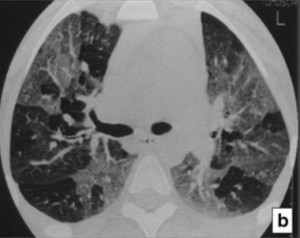

La herramienta estándar es la tomografía de alta resolución, donde aparece el signo distintivo llamado patrón de atenuación en mosaico. Al realizar una tomografía en fase espiratoria, se confirma el atrapamiento aéreo, ya que las zonas dañadas permanecen anormalmente oscuras al no poder expulsar el aire. Por su parte, la espirometría suele mostrar una mejora menor al 12% tras el uso de albuterol, confirmando que el daño es estructural y no funcional.